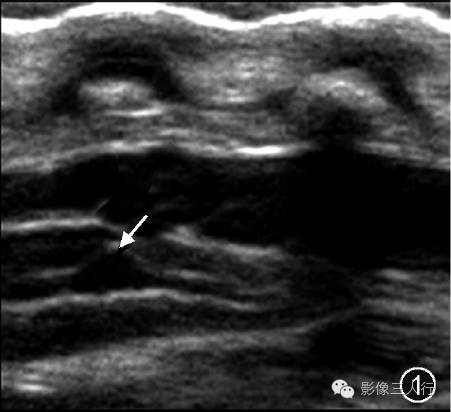

图1~3 男,5 d。超声矢状切面显示第五脑室是位于脊髓圆锥内且囊壁光滑的囊腔(图1,↑);图2为图1的示意图;矢状面T2WI显示第五脑室是位于脊髓圆锥中央的囊性扩张结构,囊内呈高信号(图3,↑)